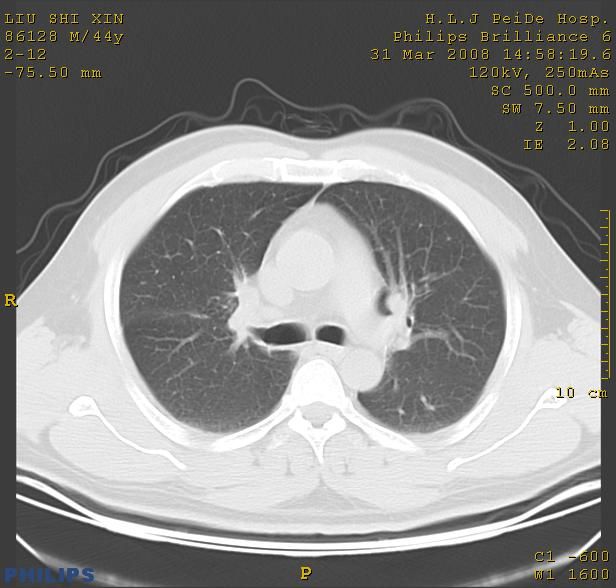

标题: CT13096:请分析胸膜下结节的影像基础是什么 有病理结果 [打印本页]

标题: CT13096:请分析胸膜下结节的影像基础是什么 有病理结果

瘢痕挛缩,胸膜牵拉,血管纠集扭曲,上叶前段支气管显示欠清,周围散在斑片影,以纵隔旁肺癌可能性大。请穿刺检查。

中心型肺癌并阻塞性肺炎及肺内转移

中心型肺癌并阻塞性肺炎、两肺及胸膜多发转移。

结节灶与血管末梢相通象转移灶;小三角状尖部有纤维索是胸膜拉扯征;纵隔旁大片实性影有点状钙化;周围有名显纤维瘢痕征可考虑瘢痕癌

本病例有病理结果是,鳞状上皮癌,胸膜下结节影病现诊断的肿大淋巴结,谢谢大家分析,请问胸膜下结节是肿大淋巴结怎么解释